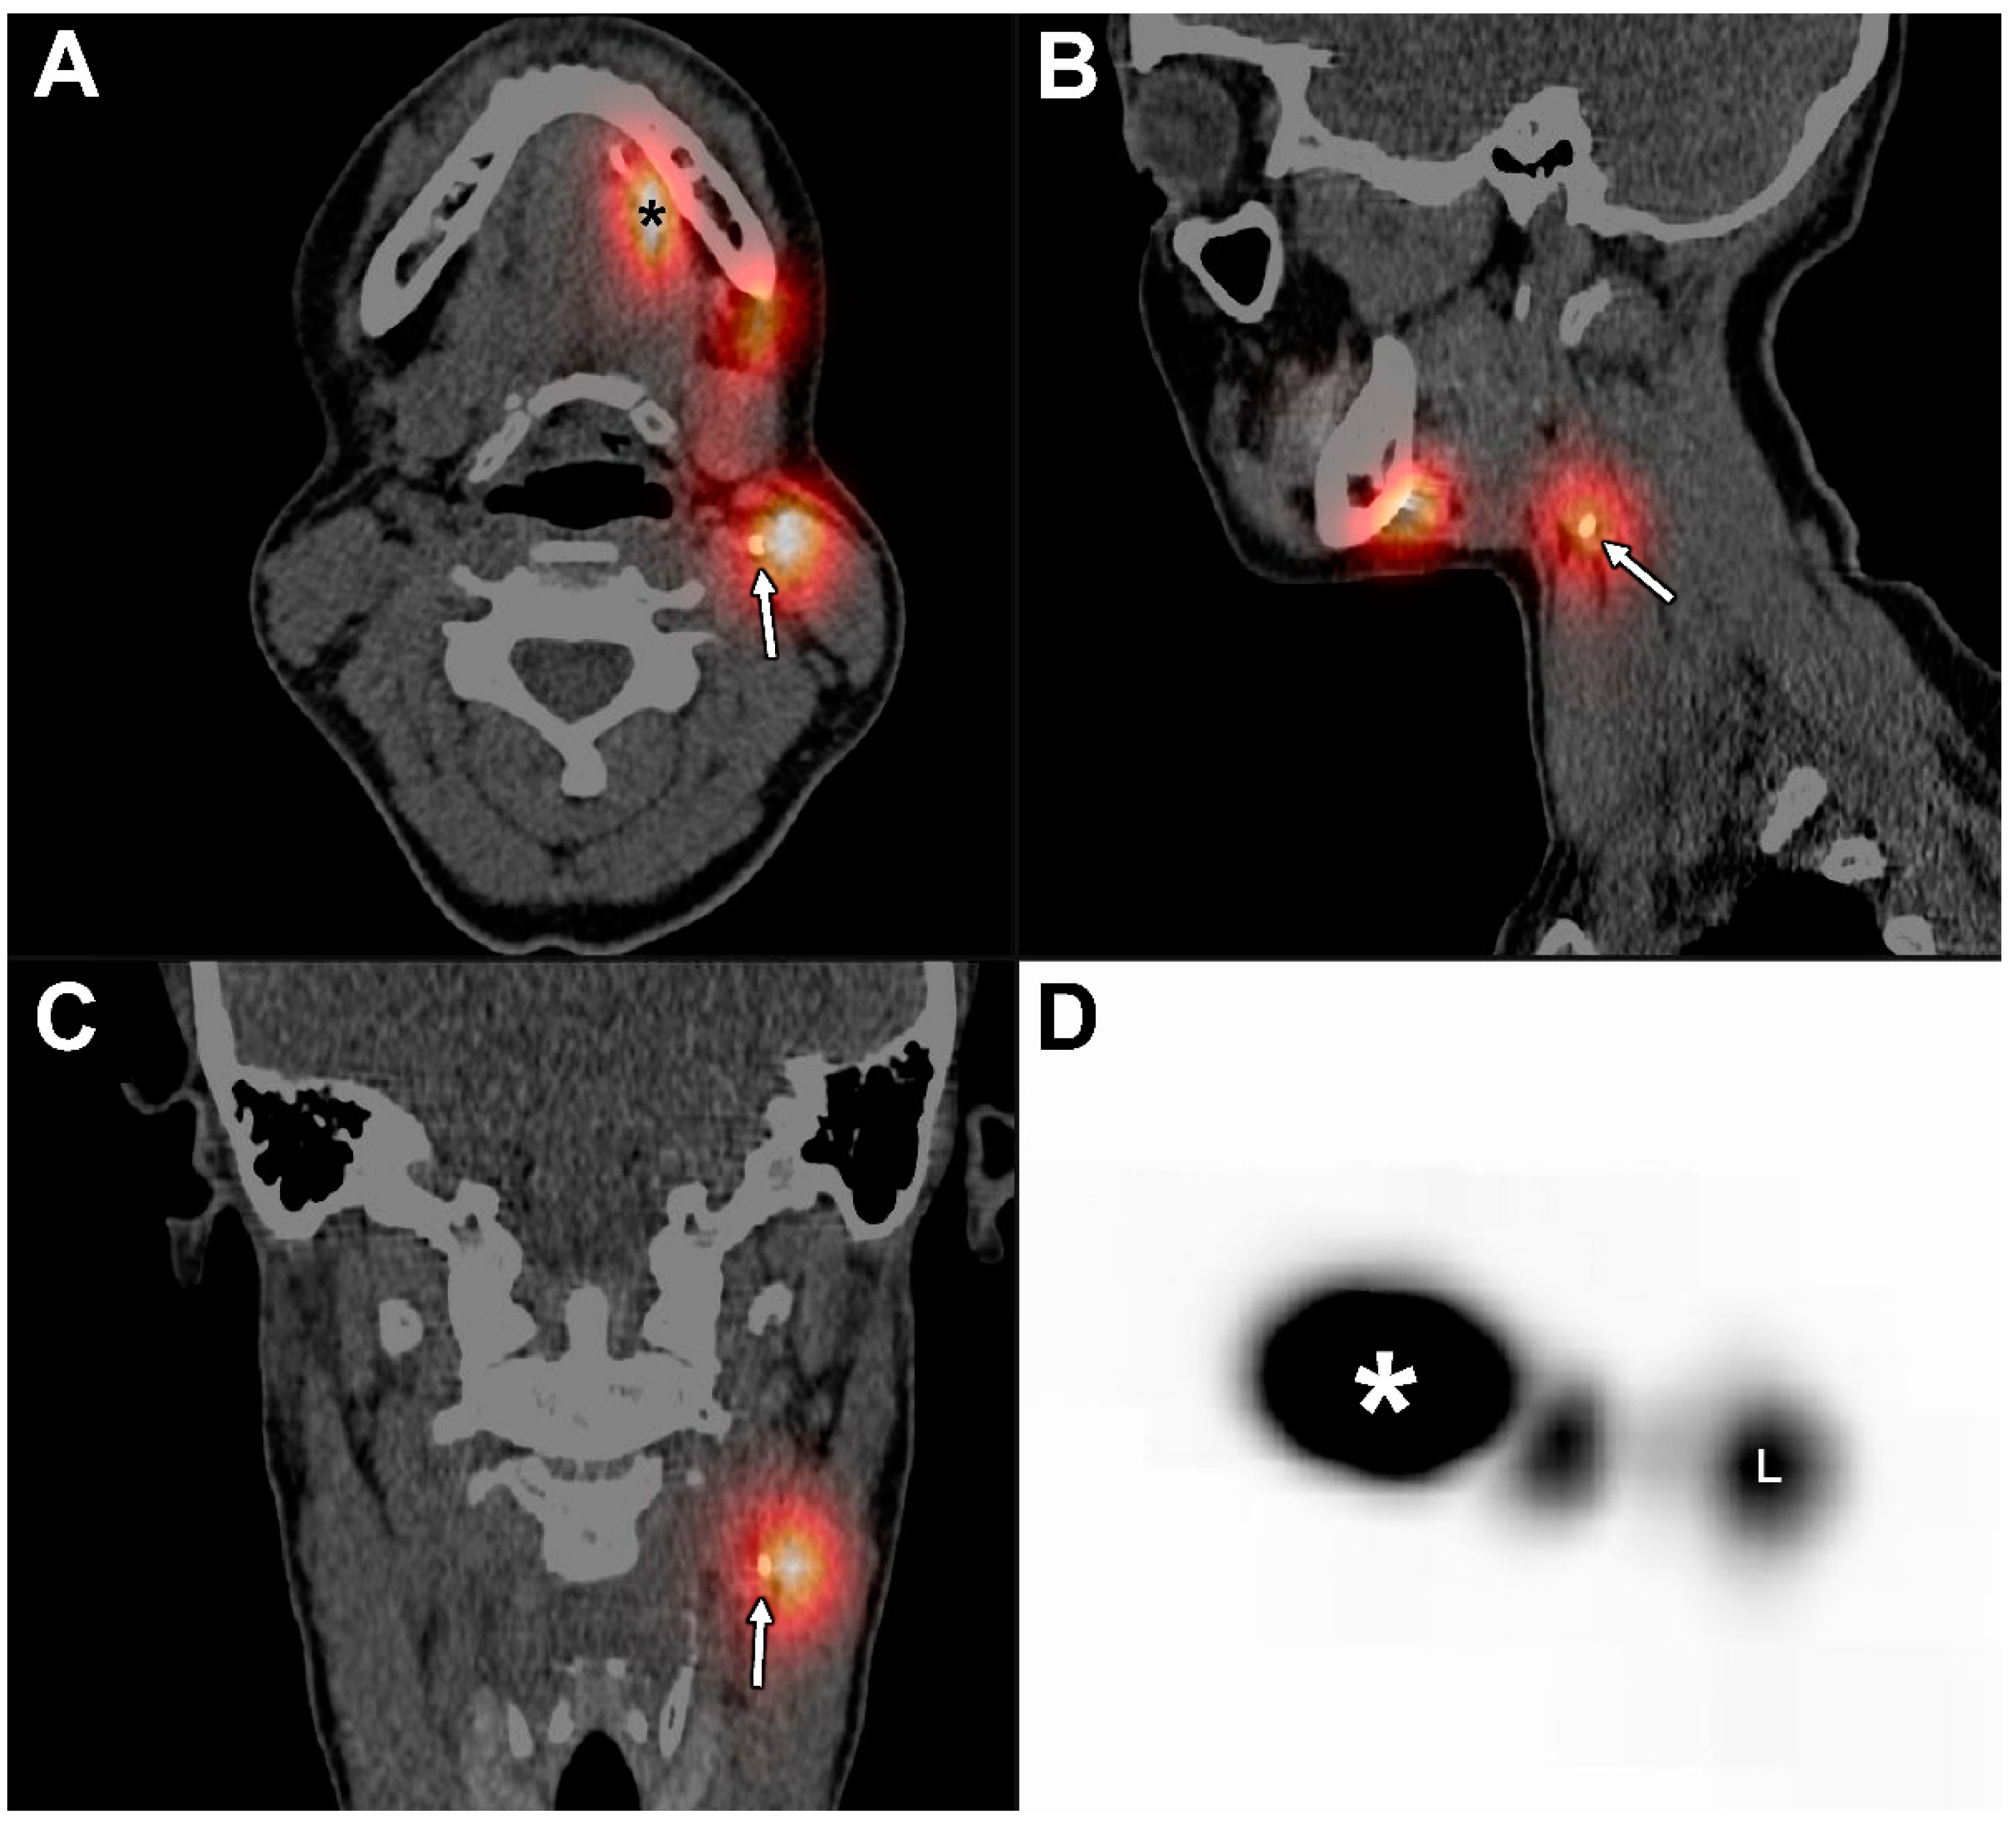

Figure 4.

Fusion of SPECT and late CTL at 120 min post-injection of Lipiodol® in the same patient (patient 6). (A) Axial plane, (B) sagittal plane, (C) coronal plane, and (D) maximum intensity projection (MIP); (*) injection site. The presence of Lipiodol® was seen in a SLN located in cervical lymph node level IIa on the left side (white arrows), as identified with SPECT, corresponding with the hotspot (L) on MIP. Conventional 99mTc-nanocolloid lymphoscintigraphy (including SPECT/CT) identified another SLN in cervical lymph node level Ib on the left side, in which no uptake of Lipiodol® could be seen on late CTL.